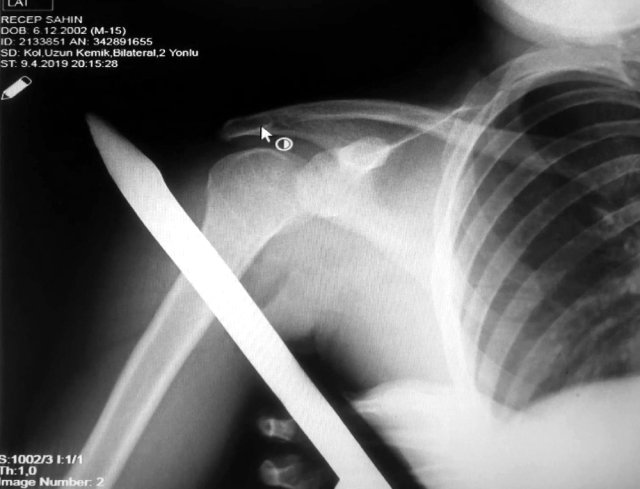

Asarcık ilçesi Emirmusa Mahallesi'nde dün meydana gelen olayda, Recep Şahin (17), cami çevresindeki korkulukların üzerinden atlarken ayağının kayması sonucu sivri uçlu demir omzuna saplandı. Demir, gencin omzunun arkasından girip ön kısmından çıktı. İhbar üzerine olay yerine gelen itfaiye, demiri keserek genci kurtardı. Genç, omzundaki demirle OMÜ Tıp Fakültesi Hastanesine kaldırıldı. Ortopedi ve Travmatoloji Uzmanı Prof. Dr. Turgut Nedim Karaismailoğlu tarafından yapılan başarılı operasyonla gencin omzundaki demir çıkarıldı.

Yaşadığı olayı anlatan Recep Şahin, "Caminin çevresindeki korkuluğun üzerinden atlarken ayağım kaydı. Korkuluk demiri omzuma saplandı. Demir omzumun arkasından girip önünden çıktı. Babamı aradım. İtfaiyeden yardım istedik. İtfaiye demiri kesti. Hastaneye kaldırıldım" dedi.

OMÜ Tıp Fakültesi Öğretim Üyesi Prof. Dr. Turgut Nedim Karaismailoğlu ise "Hastamızın ayağı kaymış ve korkuluk demiri omzuna saplanmış, arkadan girip önden çıkmış. Geldiğinde demirin ucu dışarıdaydı. Omzuna hasar vermiş. Demiri omzuna zarar vermeden çıkardık. Damar ve sinir problemi olmadan hallettik. Bu korkuluk demirlerinin daha dikkatli yapılması gerekiyor. Sivri uçlu olduklarından böyle vakalar olabiliyor. Vatandaşlarımız bu konuda dikkatli olmalı" diye konuştu.